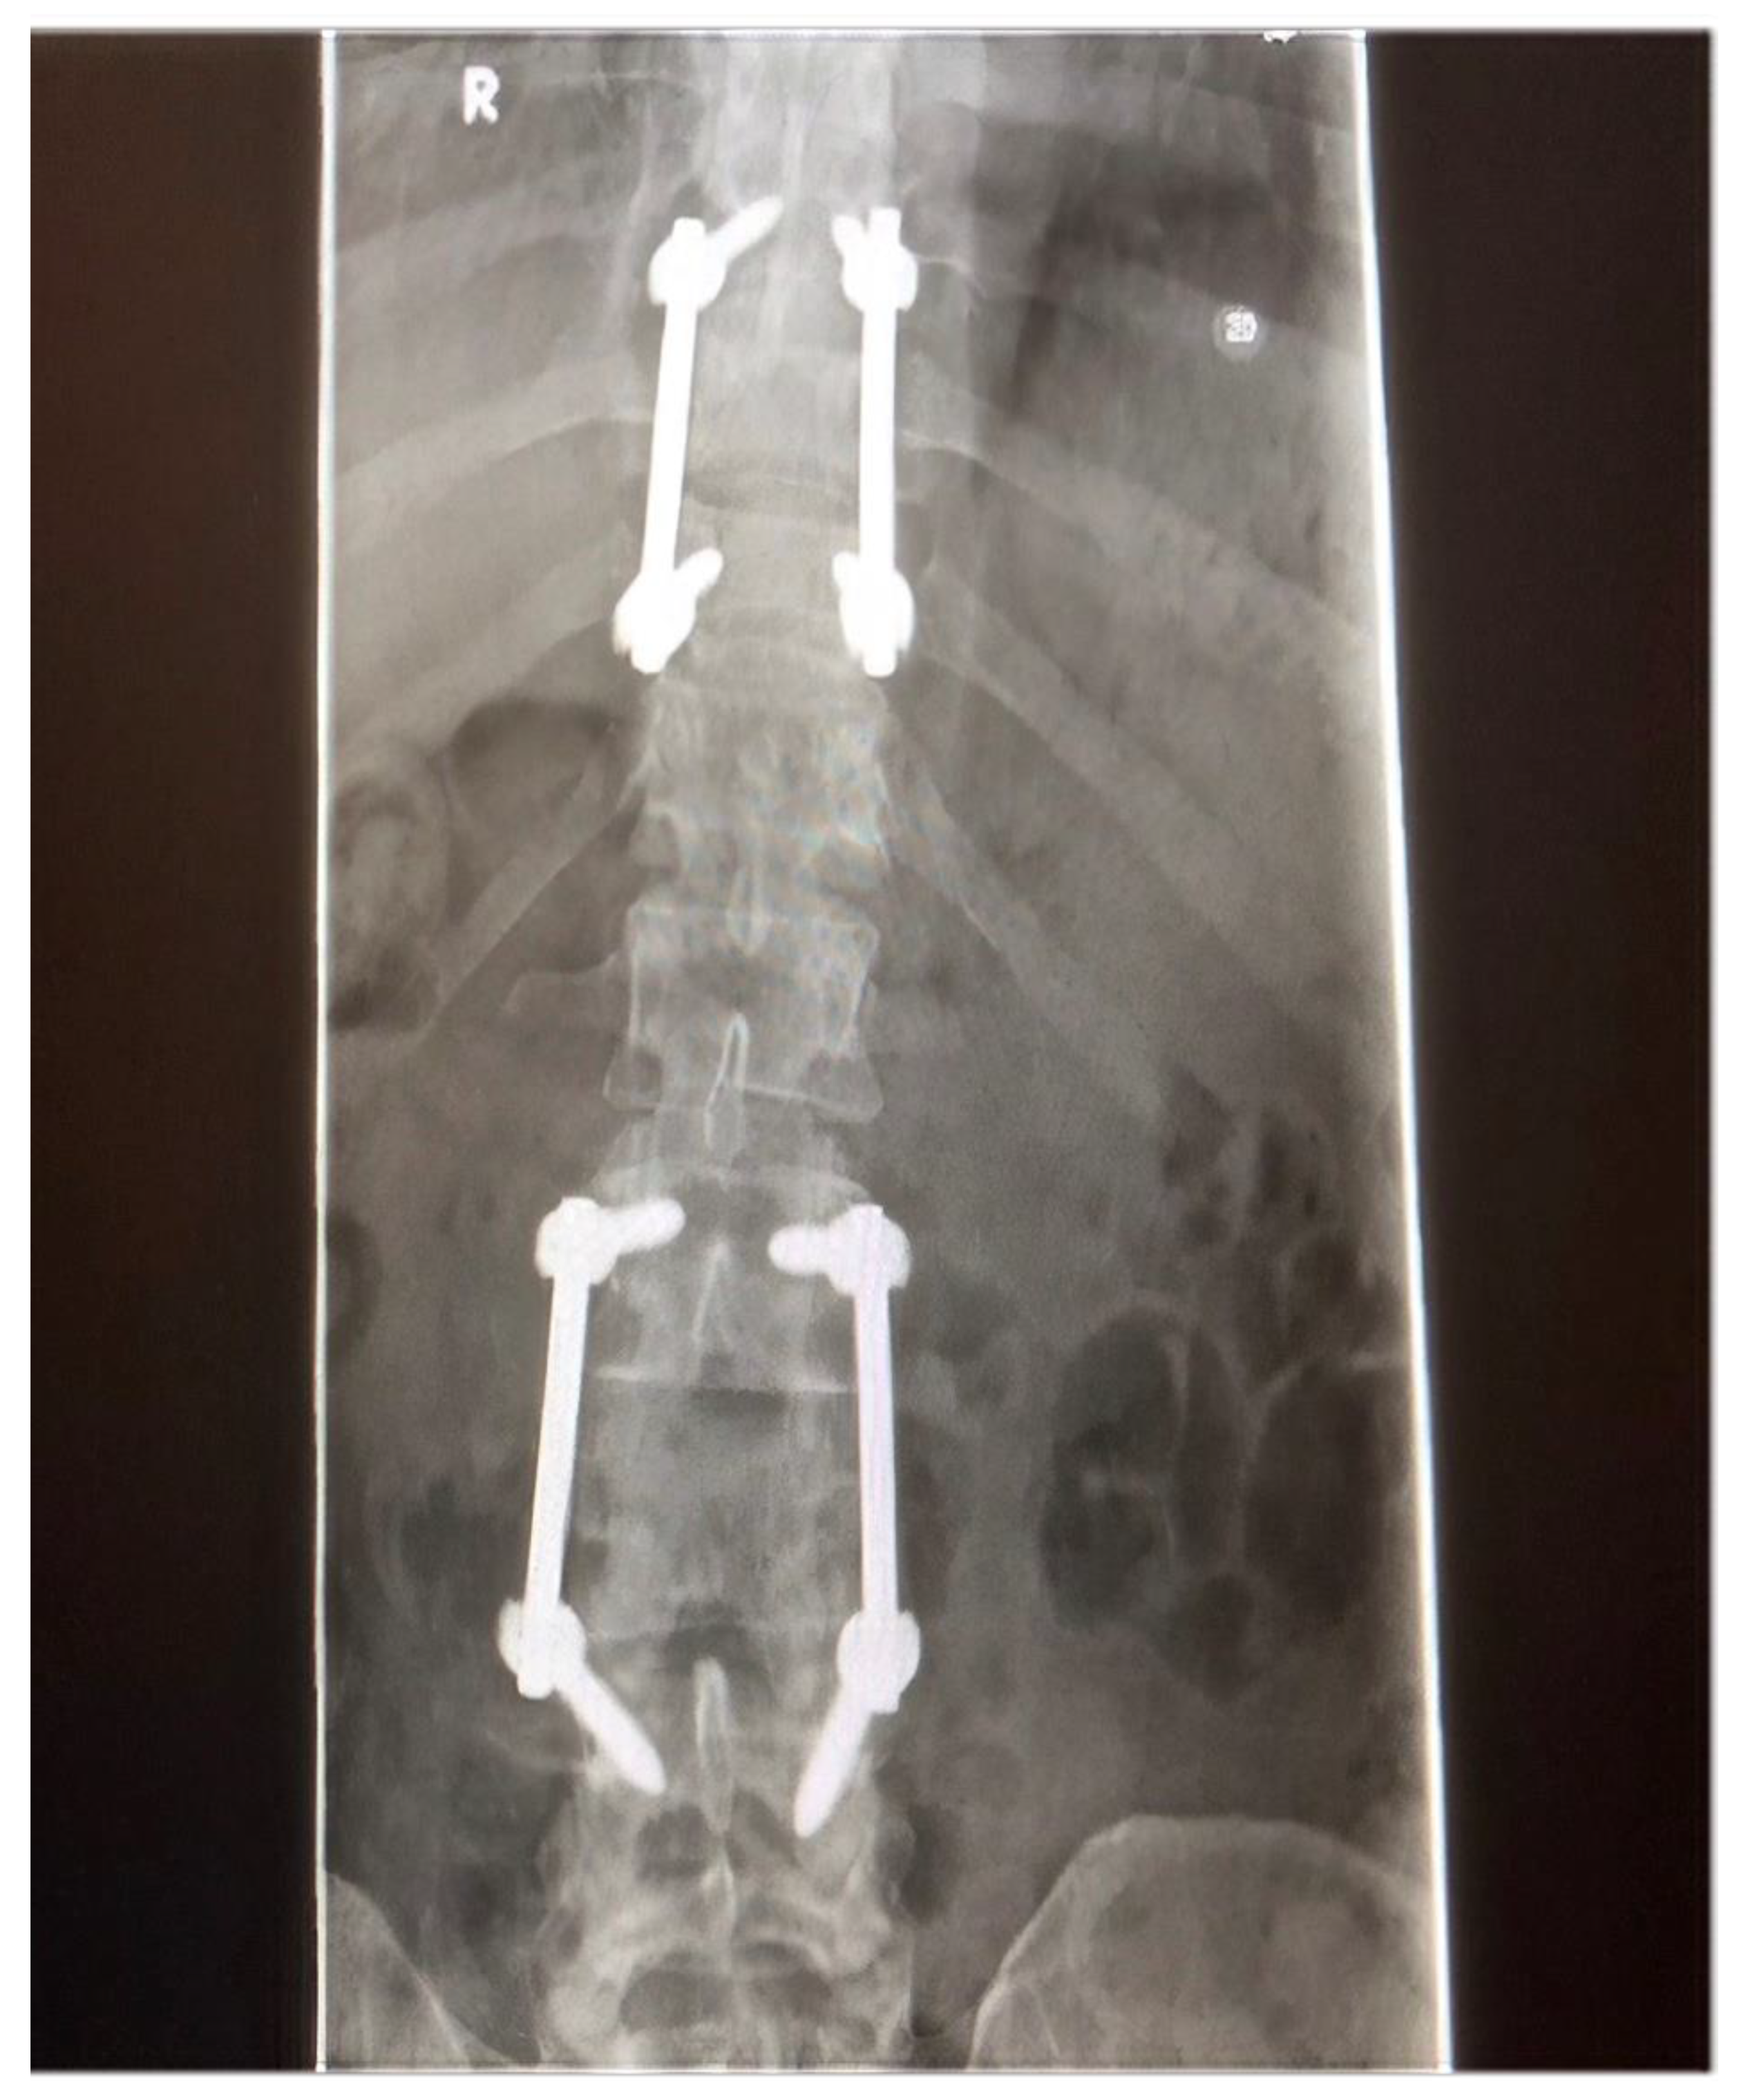

2. Case Report